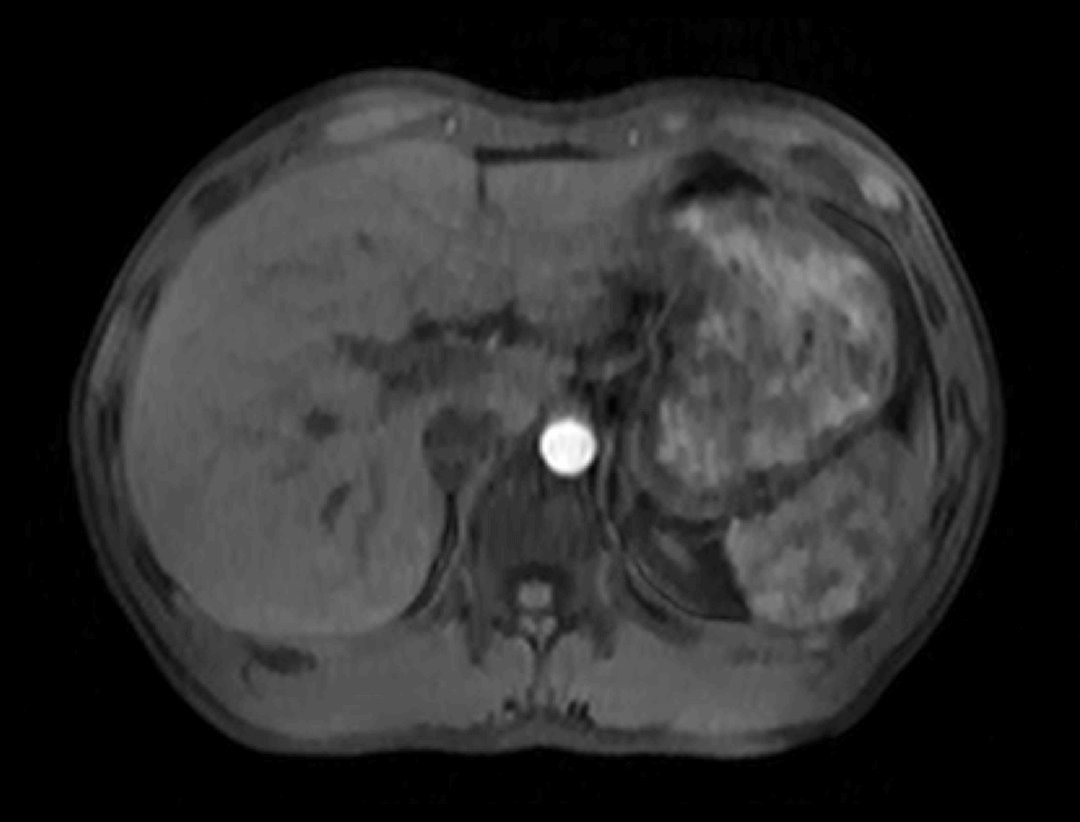

光梭®2.0成像应用于磁共振腹部动态增强扫描,可实现16倍采集加速,清晰捕捉组织信号连续动态变化,精准捕获腹部动态影像的每一瞬间,实时、全方位锁定病灶。